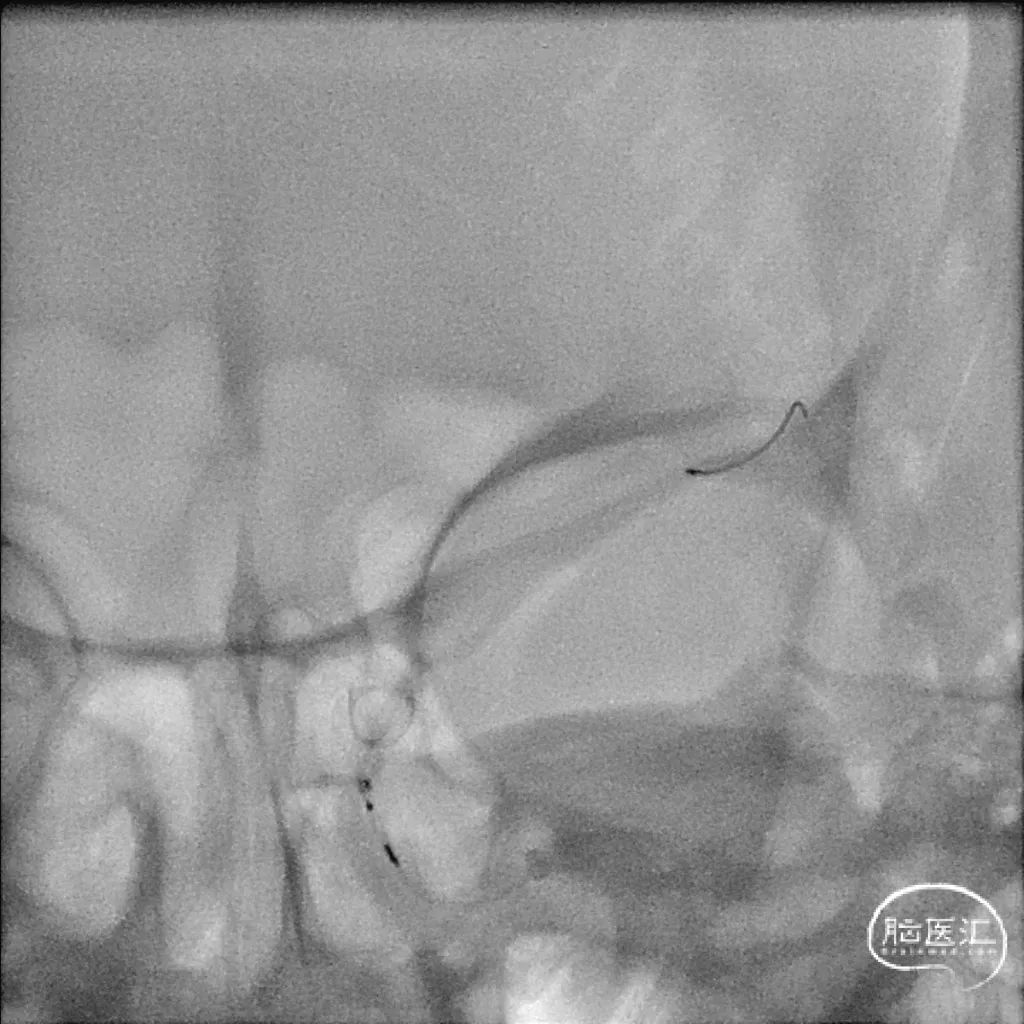

逐渐释放支架,定位。

造影,确定支架头端落点。

逐渐释放支架。

逐渐释放支架,确认贴壁良好。

逐步“按摩”,精准贴壁。

“按摩”后造影,可见瘤内造影剂滞留。

支架展开形态。